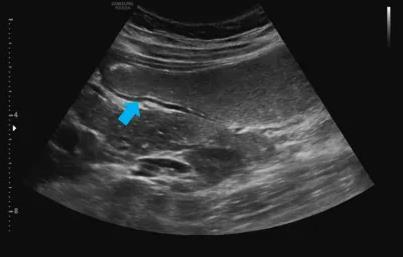

▲通过造影剂对比,可清晰显示胃壁全层结构(箭头所示)

胃肠超声造影检查具有无创、无痛苦,可重复多次检查,患者依从性好等优势,适合孕妇、儿童、老年人等不适宜做胃肠镜及胃肠镜效果欠佳的人群。另外,胃肠超声造影可较清晰显示胃肠壁层次结构及病变,与胃肠镜可达到相辅相成的效果,被视为内镜检查的重要补充手段。